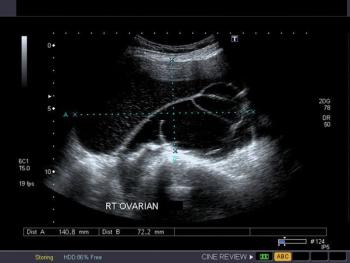

In a systematic review of UAE versus other surgical interventions for symptomatic uterine fibroids, researchers concluded that UAE offers substantial improvements in symptoms of uterine fibroids but may not help women who want to retain their reproductive potential.